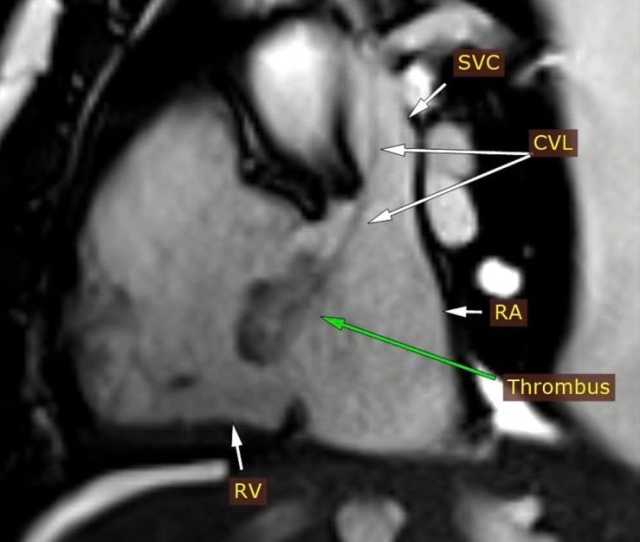

أعلن الدكتور حسان النعماني رئيس جامعة سوهاج ان فريق وحدة تصوير القلب بالرنين المغناطيسي بمستشفى سوهاج الجامعي الجديد للطوارئ، نجح في تشخيص حالة دقيقة لشاب يبلغ من العمر ٢٥ عاما يعانى من فشل بعضلة القلب واستسقاء بالبطن وآلام متكررة بالصدر، مؤكدا أن الوحدة تعد الأولى من نوعها في إقليم الصعيد، حيث أن هذه الحالة تُعد نموذجًا لما تقدمه وحدة تصوير القلب من خدمات تشخيصية متقدمة، إذ تمكنت من تحديد طبيعة الجلطة ومكانها بدقة عالية، ما ساعد الفريق الطبي في وضع خطة علاج مناسبة أنقذت حياة المريض.

وأضاف الدكتور مجدي القاضي عميد كلية الطب البشري ورئيس مجلس اداره المسشفيات الجامعيه ان التقرير الطبي اوضح بعد إجراء فحوصات الإيكو للقلب، تبين اشتباه وجود ورم بالأذين الأيمن وعلى الفور تم تحويل المريض الى وحدة التصوير الطبى للقلب واجراء رنين مغناطيسى على القلب وتبين ان المريض يعانى من التهابات بعضلة القلب وتواجد جلطة بالاذين الايمن وتم تشخيص الحالة بدقة وتلقى العلاج المناسب بقسم امراض القلب والاوعيه الدمويه.